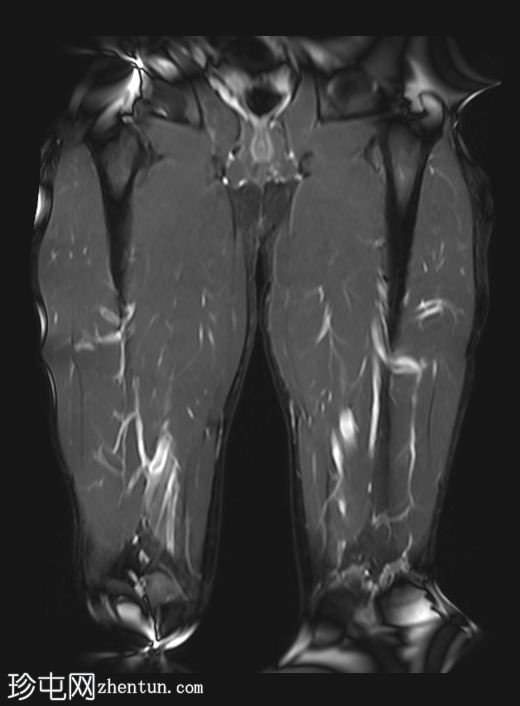

3.jpg

矢状位

T1加权像

左侧股直肌近端肌腱交界处可见异常高信号,向远端延伸约至肌长一半。

可见清晰的充满液体的分离平面,呈“靶心征”,将双羽状间接头与浅表单羽状直接头分隔开,呈现出股直肌脱套样损伤的特征性影像

间接头肌纤维与近端肌腱保持连续,未见肌腱断裂或明显回缩。

可见轻度肌间及筋膜周围水肿。病例讨论